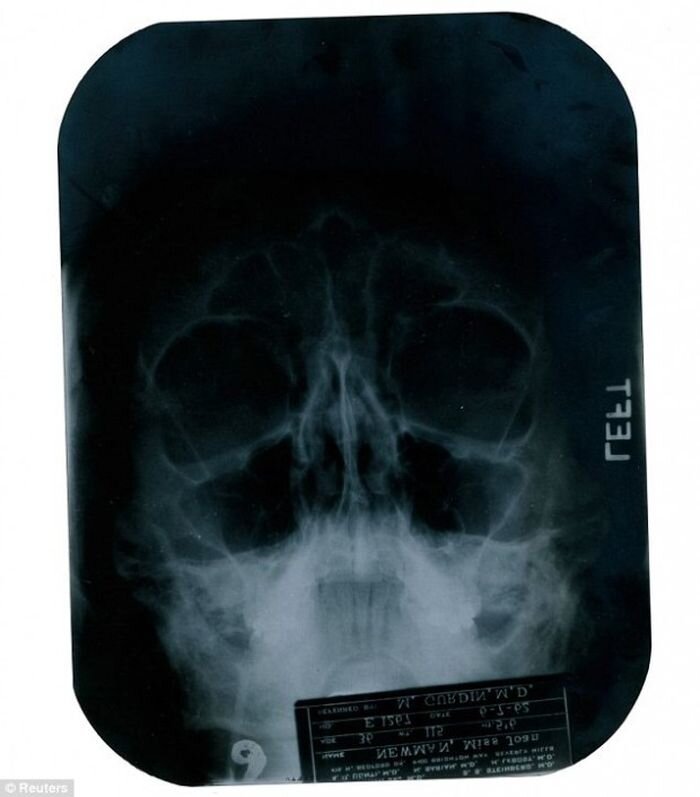

1. Актриса сделала несколько пластических операций. Долгое время это считалось легендой, или, как минимум, ничем не подтвержденной информацией. Но когда медицинские документы Мэрилин Монро были выставлены на аукцион, стало известно, что Мэрилин Монро были сделаны ринопластика, изменена форма подбородка и поправлен нижний край волос на лбу. И сделано все было так, чтобы никто не заметил резких изменений в облике актрисы, что для пластической хирургии того времени было настоящим чудом.

Рентгеновский снимок головы Мэрилин Монро, выставленный на аукцион